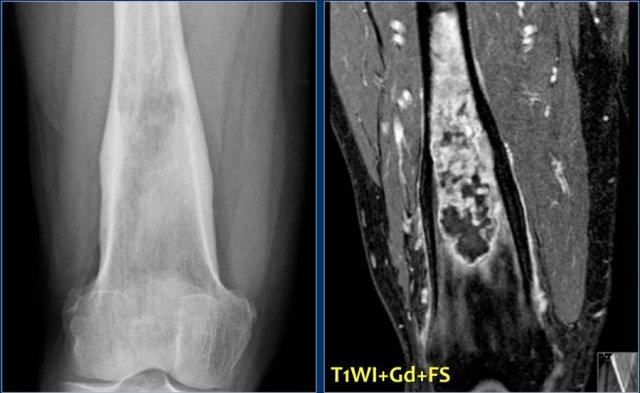

Hình ảnh cho thấy một tổn thương vôi hóa ở đầu gần xương chày mà không có đặc điểm đáng ngờ.

Đây rất có thể là một u sụn nội xương (enchondroma).

Có những đặc điểm khác ủng hộ chẩn đoán sarcoma sụn độ thấp như xạ hình xương dương tính và hình ảnh xói mòn nội màng xương trên MRI (không hiển thị).

Sarcoma sụn đã được chẩn đoán qua sinh thiết.